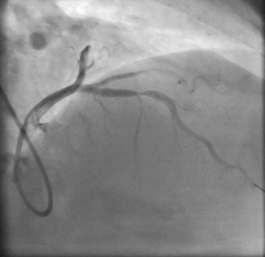

XCA is particularly beneficial in diagnosing coronary artery stenosis (CAS), a condition characterized by the narrowing of the coronary arteries due to plaque buildup [8]. The procedure involves inserting a catheter through the femoral artery into the heart, followed by the injection of contrast material to visualize the coronary vessels. Meanwhile, the pressures inside the heart are monitored, and its contractile function is tested by introducing contrast material into the left ventricle. Following the examination, 4-6 hours of bed rest are usually recommended. Typically, XCA provides high-resolution images, like the ones shown in Figure 1 [9], that allow physicians to detect stenotic areas in coronary arteries and evaluate their severity.

Figure 1. Coronary angiography images and areas of stenosis for a CAS patient [9]